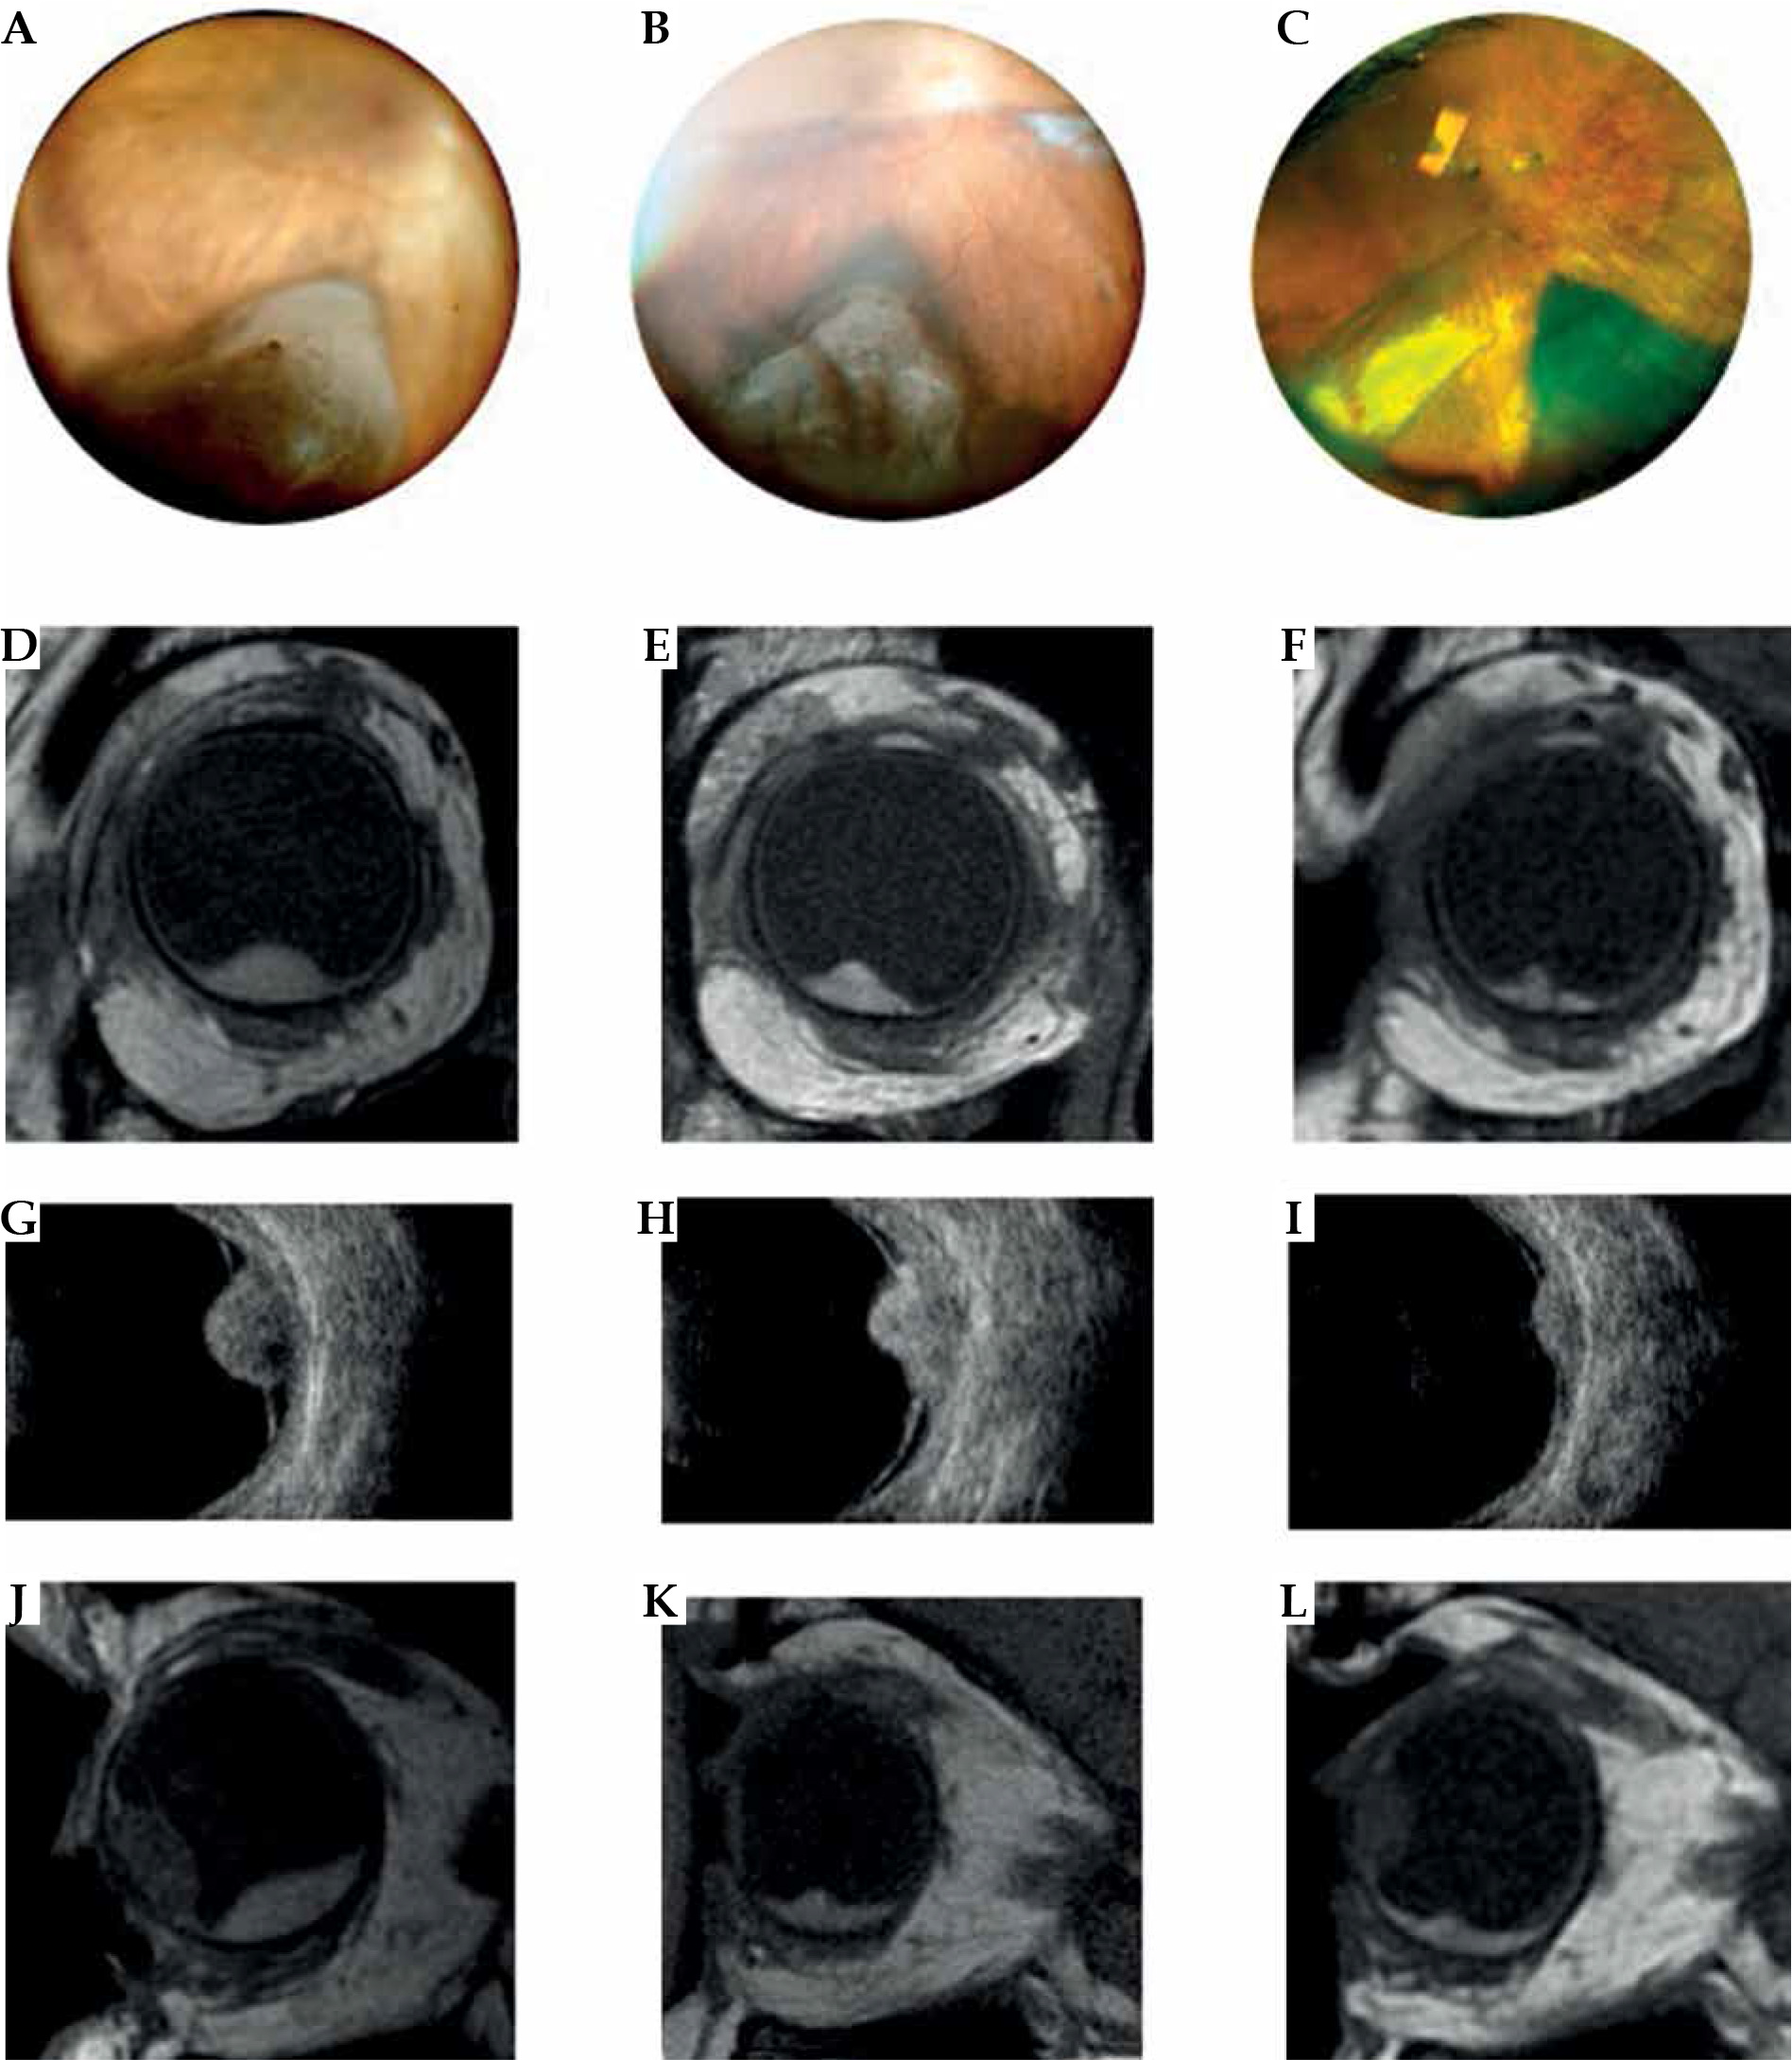

Fig. 3

Case 3. A-C) Fundus photograph of a choroidal melanoma located inferiorly at diagnosis and at 1 and 3 years after treatment. Note that the images do not allow to locate the anterior margin of the tumor. D-I) MRI and ultrasound images showing the transversal extension of the tumor at diagnosis and at follow-up. J-L) Sagittal magnetic resonance imaging in a T1-weighted image at diagnosis and at follow-up. MRI is particular useful in measuring longitudinal diameter in cases of choroid melanoma with anterior extension into the ciliary body and iris

Case 3

A 65-year-old woman was referred to our hospital with a chief complaint of visual field defect in her left eye. Her corrected visual acuity was 20/20 in both eyes. Slit lamp examination showed a large darkly pigmented mass in the inferior quadrant. B scan and UBM examination were performed and revealed a tumor of choroidal origin extended from the root of the ciliary body to the equatorial portion of the bulb, with a domed appearance, a homogeneous acoustic structure, and a medium-low reflectivity. It was associated with perilesional retinal lift with signs of neo-vascularization. The lesion had a thickness of 6 mm (A and B scan) and 10.7 mm of basal transversal diameter. Due to the ciliochoroidal location, B scan and UBM ultrasound examination were not a useful tool for measuring antero-posterior diameter. MRI measured a longitudinal diameter of 18 mm. The diagnosis was ciliochoroidal melanoma stage T3N0M0, and the patient underwent IRT with 125I plaque COMS 18 (prescribed dose 85 Gy) in 2013. Follow-up imaging was performed using both ultrasound and MRI, and showed a progressive regression of the tumor. The best corrected visual acuity at 3 years’ follow-up was 20/32. The patient is still alive, with no evidence of a recurrence.